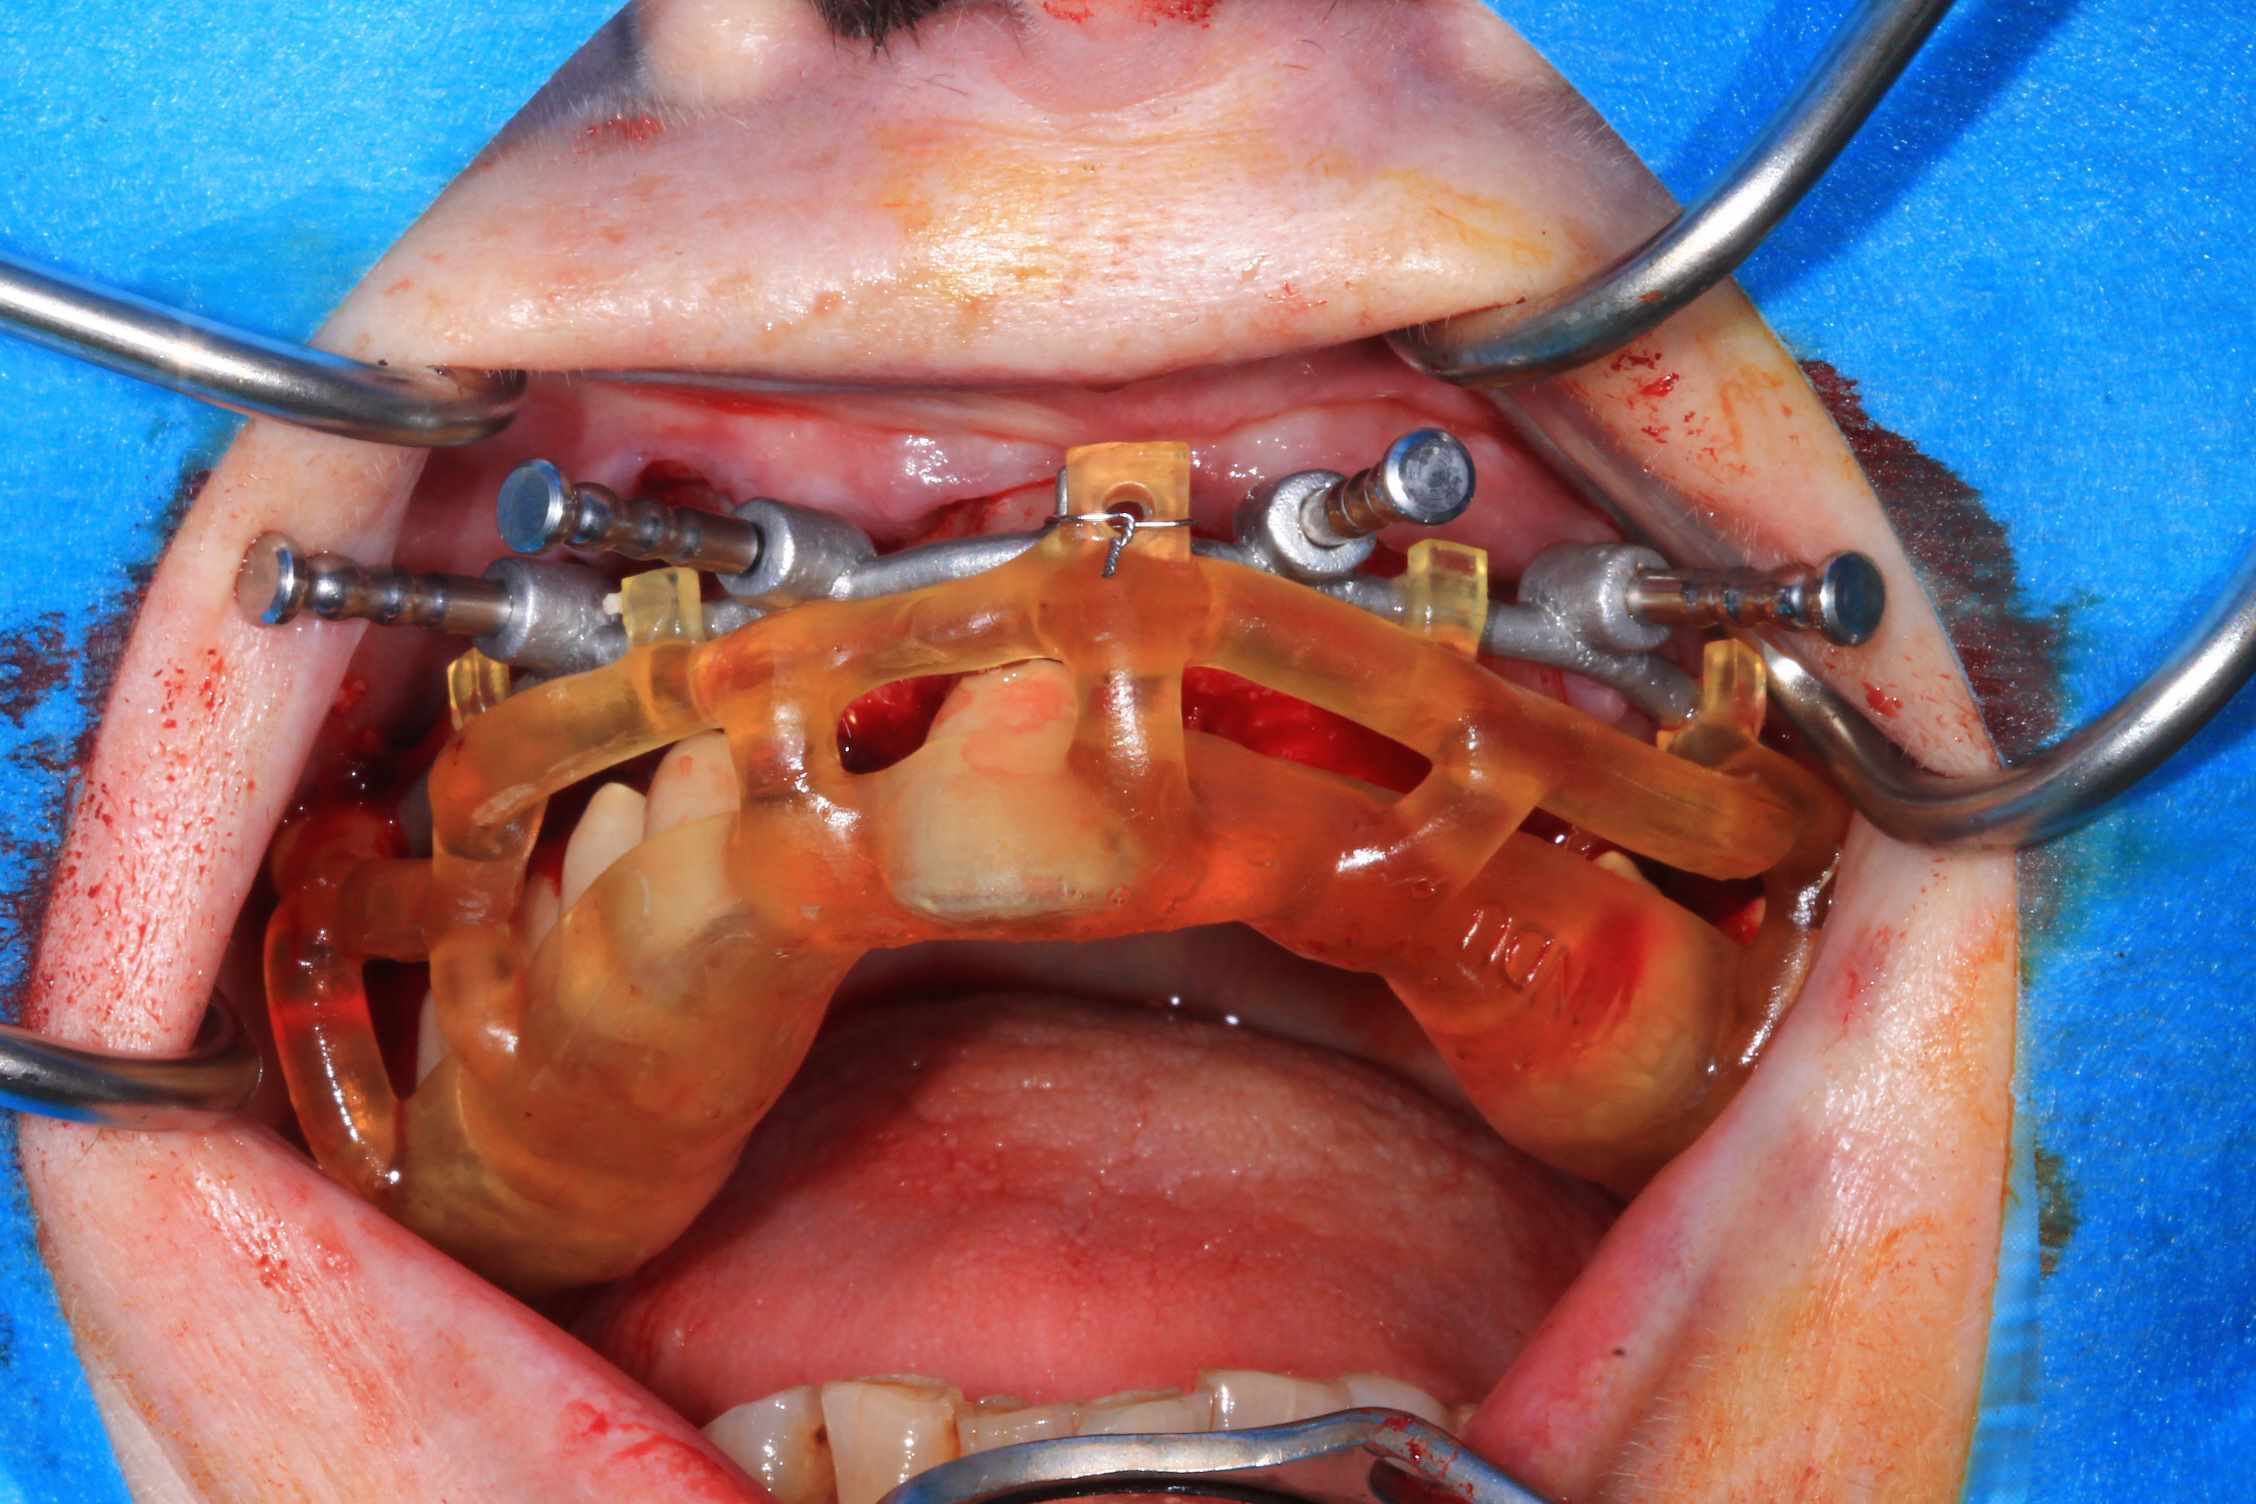

Guide métal avec support clavette, os assez fin : il est prévu un sticky bone complet : donc : lambeau avant extraction, positionnement du guide base et forage des clavettes, positionnement du guide implant, pose des piliers MU, controle des axes prothétique avec le guide pilier, collage des piliers prov sur le bridge a armature métal, occlusion nickel, sticky bone et PRF, sutures suspendues.

T’as quand même une sacrée déviation des implants / à la planification…..

Ça se voit déjà avec les implants posés à travers le guide de forage métallique qui est amha trop permissif

Et c’est confirmé par ton guide pour les piliers multiunits qui n’est même pas à fond (clavette antérieur pas mise….enfin certainement impossible à mettre)

Mais tu as raison, il y avait un peu trop de jeu au niveau du guide .

C’est le premier entièrement métallique que je fais imprimer ( Fridentech ). Il faut que je fasse un modèle avec plusieurs diamètres pour avoir le meilleur ajustage . Je pense que le mieux serait d’insérer une douille ETK. C’est ce que fait Dimitri avec ses guides métalliques codiagnostic.

Pour le guide pilier , c’était pile, mais je n’avais pas fais la photo. Je l’ai remis vite fais ( et mal ) pour la photo.

Le guide pilier est la réplique du bridge prov , en plus light pour une meilleure visibilité, donc, si je n’avais pas pu bien mettre le guide pilier, cela aurait été pire avec le bridge prov.

Mais tu peux me faire confiance.Le bridge prov était nickel, avec la clavette en place, sans que je ne doive meuler les puits préparés.